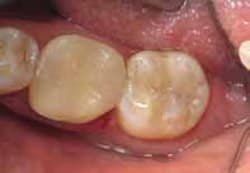

A 42-year-old male was scheduled to have two Class II posterior direct composite restorations on teeth Nos. 18 and 19 after radiographs revealed caries under old restorations (Figure 2). A 1556 carbide bur was used to remove the old restoration and caries, as well as to prepare the cavity. When composite is the restorative material to be used, a traditional G.V. Black geometrical preparation is not necessary, because composite does not require minimum depth, minimum width, or mechanical retention like amalgam does. The key is to fully remove the caries in the most tooth-conserving fashion.

Because the preparation was more than 3 mm deep, a thin layer of resin-modified glass ionomer light-cure liner (Ionoseal, VOCO, https://www.voco.com) was used to protect the pulp. The enamel cavosurface margin was etched with phosphoric acid for 15 seconds and thoroughly washed with air and water. After air drying without desiccating, a self-etch bonding system (iBond®, Heraeus Kulzer) was used for the preparation according to the manufacturer’s instructions. The first layer of bonding agent was placed and agitated for 20 seconds, followed by good air drying for 5 seconds, then light-cured (Figure 3).